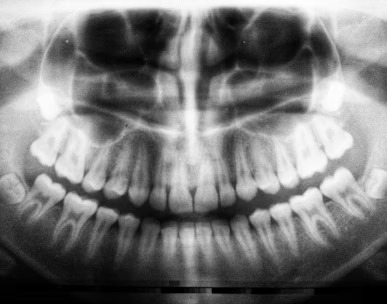

We are a dental office dedicated to serving the community with exceptional oral care in a welcoming environment. With our expertise, cutting-edge technology, and commitment to patient comfort, we strive to provide the best dental experience for our patients.